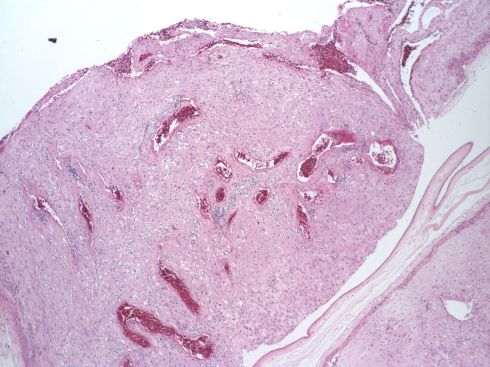

We found that even in this sample of free fetal membranes, a lesion suspected to be atherosis could be incomplete trophoblast remodeling (Figs 36-37).

Fig 36: Similar to the sample in slide 35 there is a spiral artery with a dilated segment. The sample was labeled 10 for identification of the corresponding microscopic sample.

Fig 37: The vessel identified as number 10 demonstrates dilated segments of spiral artery from medial muscle destruction, but this is due to cytotrophoblast that has migrated into the parietal decidua (arrows). (H&E, 10x)